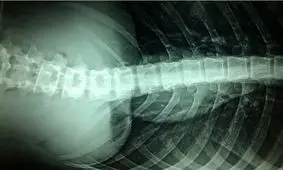

پژوهشگران آمریکایی موفق شدهاند روش جدیدی را برای کمک به بهبودی آسیبهای نخاعی ارائه دهند.

با اتمام طرح کلان ملی «ساخت سیستم پروتز عصبی پاراواک» در مرکز بالینی بیماران ضایعات نخاعی بیمارستان رفیده کاربردی…